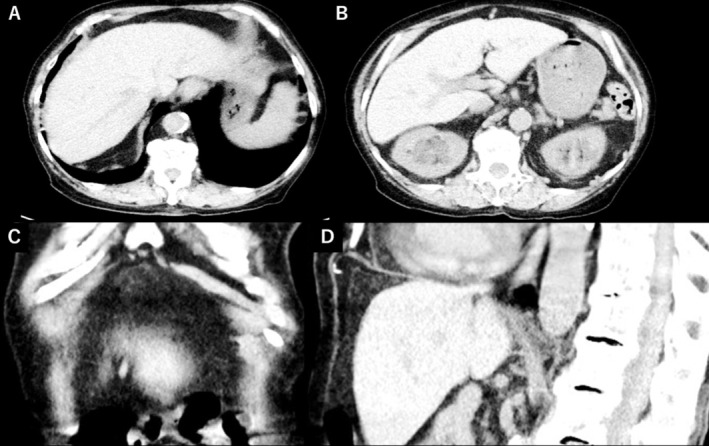

哮喘相关的非手术气腹极为罕见。本病例强调,即使没有腹部症状,自由空气也可能完全由哮喘加重引起,在排除手术原因后,不禁食的保守治疗就足够了。

Asthma-related nonsurgical pneumoperitoneum is extremely rare. This case highlights that even without abdominal symptoms, free air may result solely from asthma exacerbation, and conservative treatment without fasting can be sufficient after surgical causes are excluded.